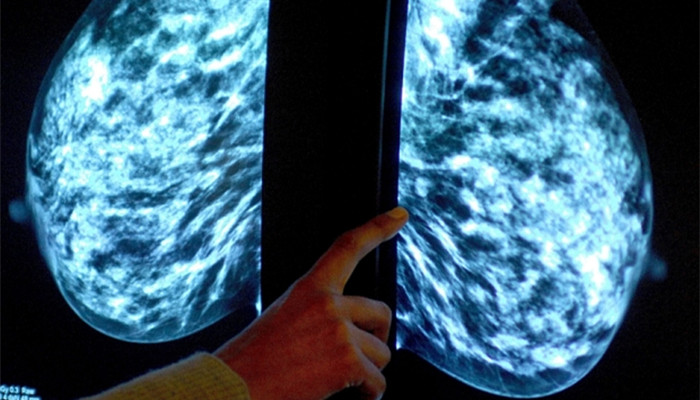

科学家们认为,通过低次数的化疗来控制癌症可能会比试图杀死癌细胞更加有效。

这种尚存争议的方法称,如果癌症病人长期与疾病共存,存活下来的几率可能更大。

目前癌症治疗经常采取积极疗法,通过高频次的化疗试图尽可能多地杀死肿瘤细胞。

一队由罗伯特•盖滕比博士(Dr Robert Gatenby)带领、来自佛罗里达州坦帕莫菲特癌症中心和研究院(H Lee Moffitt Cancer Centre and Research Institute)的美国科学家进行了一项测试。他们使用化学药物紫杉醇,来治疗患有两种不同乳腺癌的老鼠。

盖滕比博士在《科学转化医学》(Science Translational Medicine)期刊上写道:“我们的实验结果表明,这种自适应治疗策略可以被改编成临床影像,或将使乳腺癌患者的“疾病无进展生存期”延长。